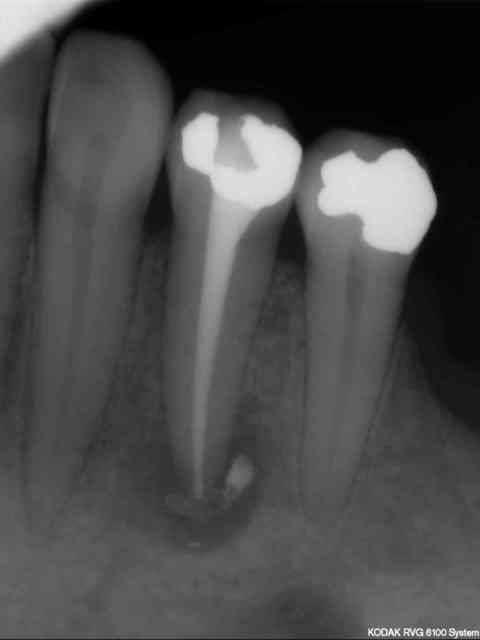

Patiente consulte avec une cellulite carabiné sur 44; trépanation -antibio, hydoxyde de calcium à plusieurs reprises puis traitement endo définitive.

Après tous ces traitements, je ne pense pas que j'arriverai finalement à la sauver car un nouvel épisode infectieux s'est encore déclaré.

Trois mois séparent les deux radios.

Je vais extraire d'ici quelques jours puis implantation plus tard.

Je ne veux pas faire d'implantation immédiate même avec un curetage soigneux de la lésion, mais je souhaite raccourcir au maximum les délais pour préserver la crête vestibulaire, les papilles, etc...